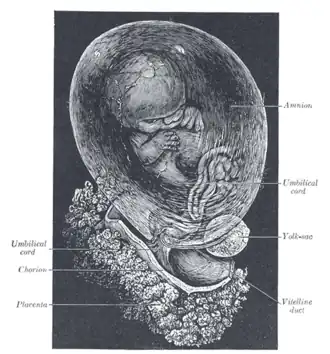

Human fetus enclosed in the amnion | |

In humans and other therian mammals, the chorion is one of the fetal membranes that exist during pregnancy between the developing fetus and mother. The chorion and the amnion together form the amniotic sac. In humans it is formed by extraembryonic mesoderm and the two layers of trophoblast that surround the embryo and other membranes;[1] the chorionic villi emerge from the chorion, invade the endometrium, and allow the transfer of nutrients from maternal blood to fetal blood.

Blood is carried to the villi by the paired umbilical arteries, which branch into chorionic arteries and enter the chorionic villi as cotyledon arteries. After circulating through the capillaries of the villi, the blood is returned to the embryo by the umbilical vein. Until about the end of the second month of pregnancy, the villi cover the entire chorion, and are almost uniform in size; but, after this, they develop unequally.

The part of the chorion that is in contact with the decidua capsularis undergoes atrophy, so that by the fourth month scarcely a trace of the villi is left. This part of the chorion becomes smooth,[2] and is named the chorion laeve (from the Latin word levis, meaning smooth). As it takes no share in the formation of the placenta, this is also named the non-placental part of the chorion. As the chorion grows, the chorion laeve comes in contact with the decidua parietalis and these layers fuse.

The villi at the embryonic pole, which is in contact with the decidua basalis, increase greatly in size and complexity, and hence this part is named the chorion frondosum.[2]

Thus the placenta develops from the chorion frondosum and the decidua basalis.